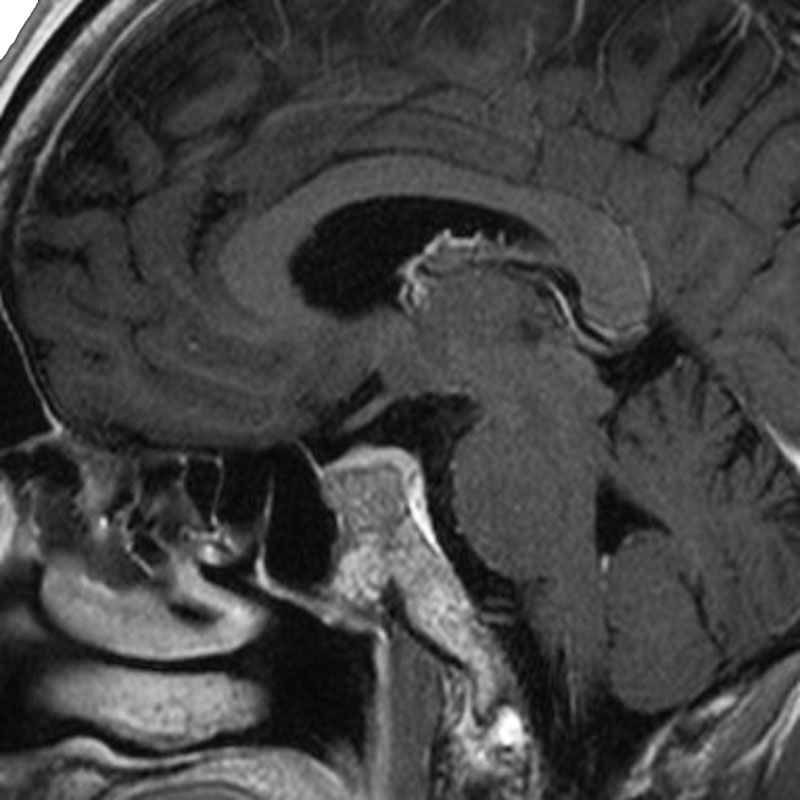

脳動脈瘤(Rt.IC)

フローダイバーター留置術

松田/濵田/元永